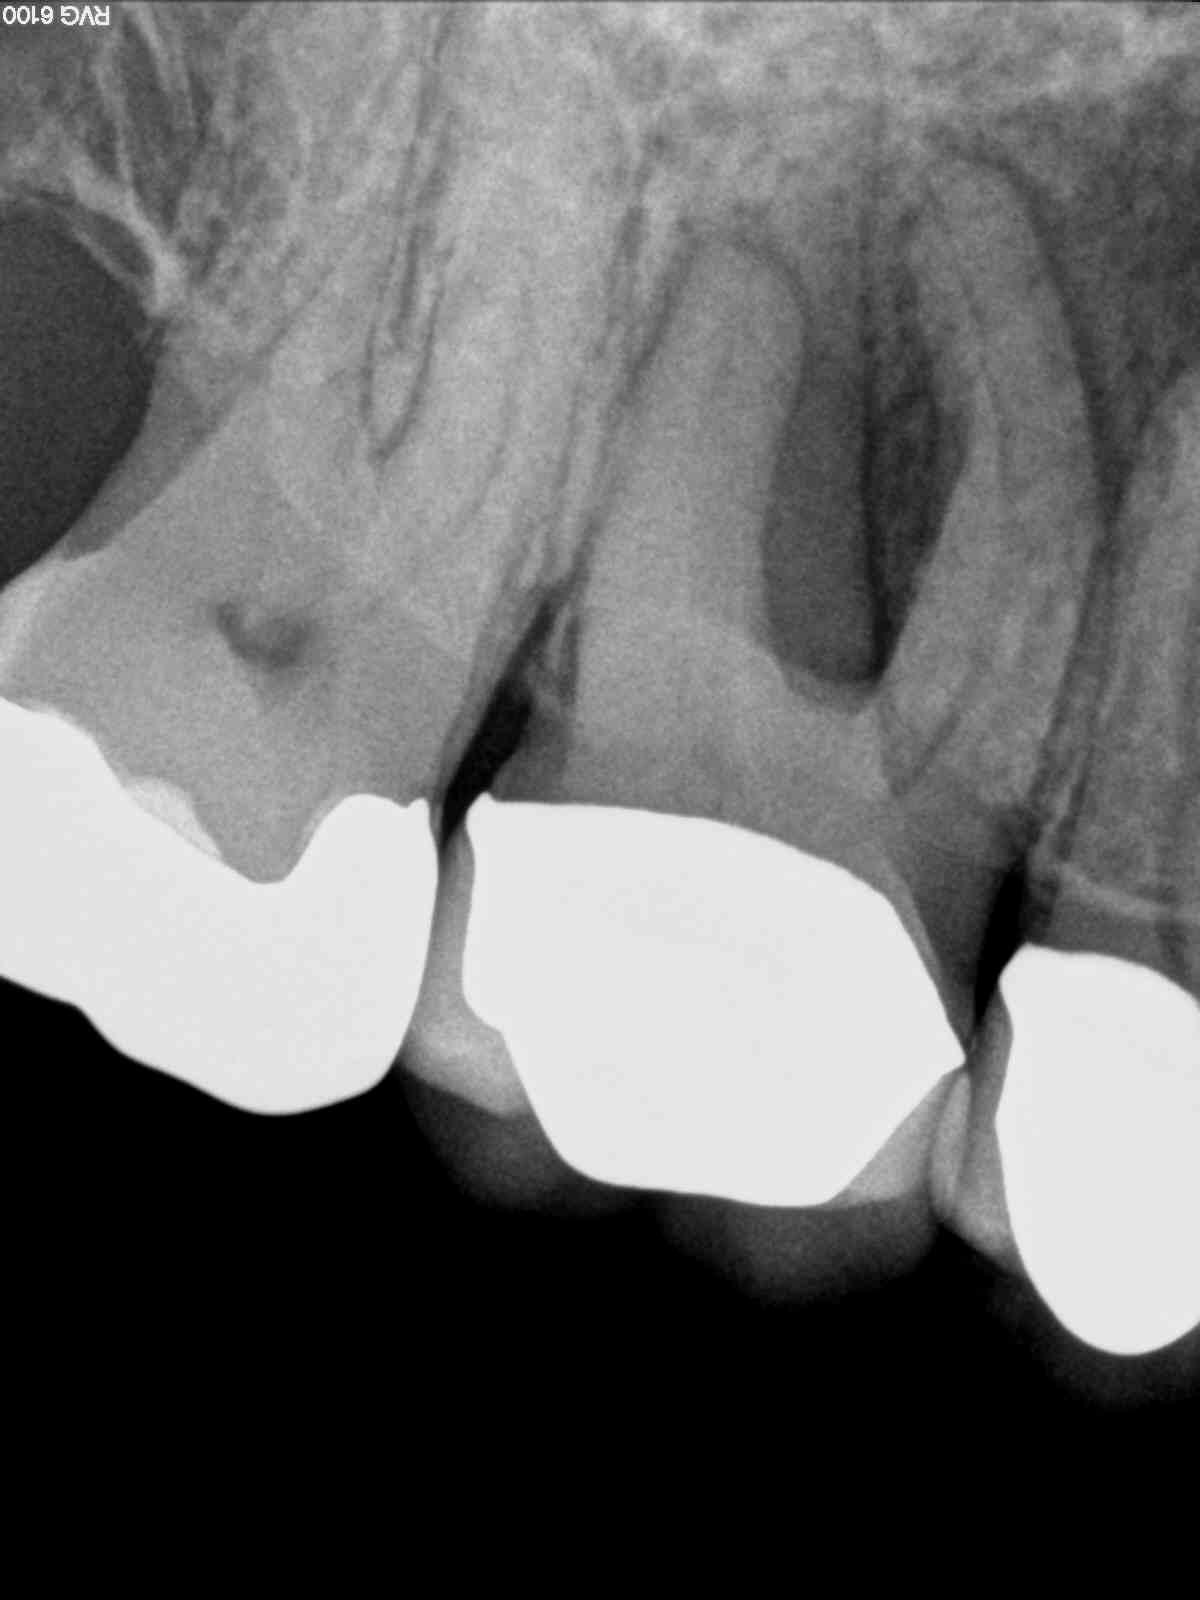

Endo-Paro-Läsion